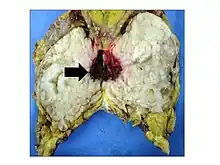

Phyllodes tumors may be considered benign, borderline, or malignant depending upon their histological features, including stromal cellularity, infiltration of the epithelial-stromal interface, and mitotic activity.[15] Due to their propensity to metastasize and grow quickly, almost all phyllodes tumors are regarded as having malignant potential and treated accordingly.[15] A large case series from the MD Anderson Cancer Center reported the incidence of each type of phyllodes tumor as benign (58%), borderline (12%), and malignant (30%).[16]

Malignant phyllodes tumors can behave similarly to sarcomas leading to development of blood-borne metastases.[16] Approximately 10% of phyllodes tumor develop distant metastases and this occurrence is higher (20%) in patients with histological-identified malignant tumors.[16] The most common site for distant metastases include the lung, bone, and abdominal viscera.[17] In more insidious cases, the parotid region has also been described in literature.[18]